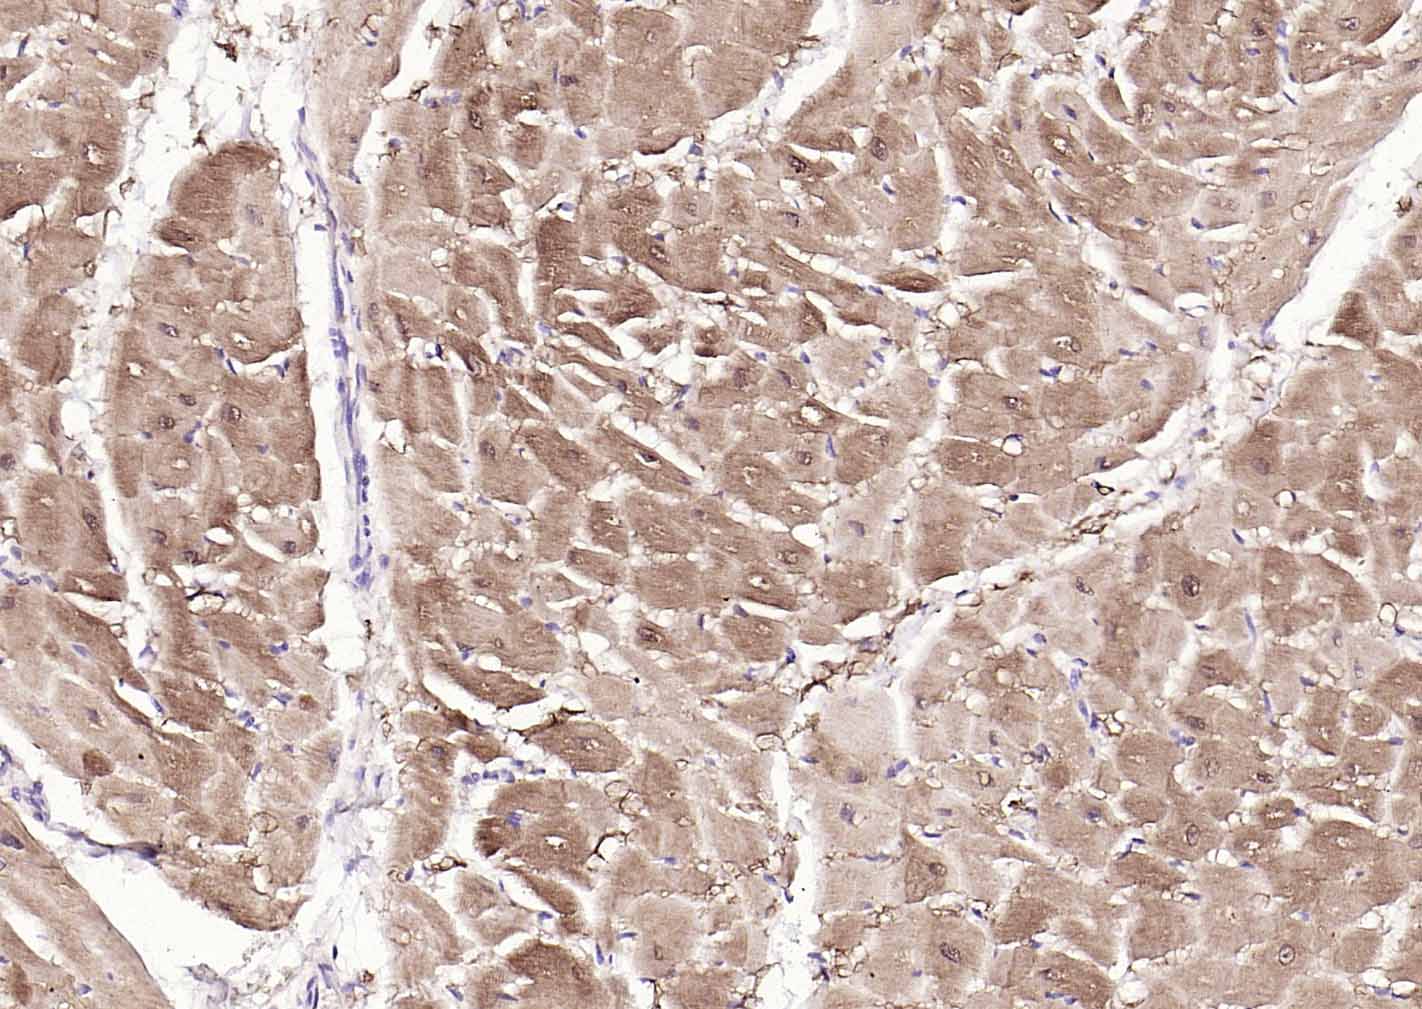

Paraformaldehyde-fixed, paraffin embedded (human heart); Antigen retrieval by boiling in sodium citrate buffer (pH6.0) for 15min; Block endogenous peroxidase by 3% hydrogen peroxide for 20 minutes; Blocking buffer (normal goat serum) at 37°C for 30min; Incubation with (S100A1 ) Polyclonal Antibody, Unconjugated (bs-41209R) at 1:200 overnight at 4°C, followed by operating according to SP Kit(Rabbit) (sp-0023) instructionsand DAB staining.